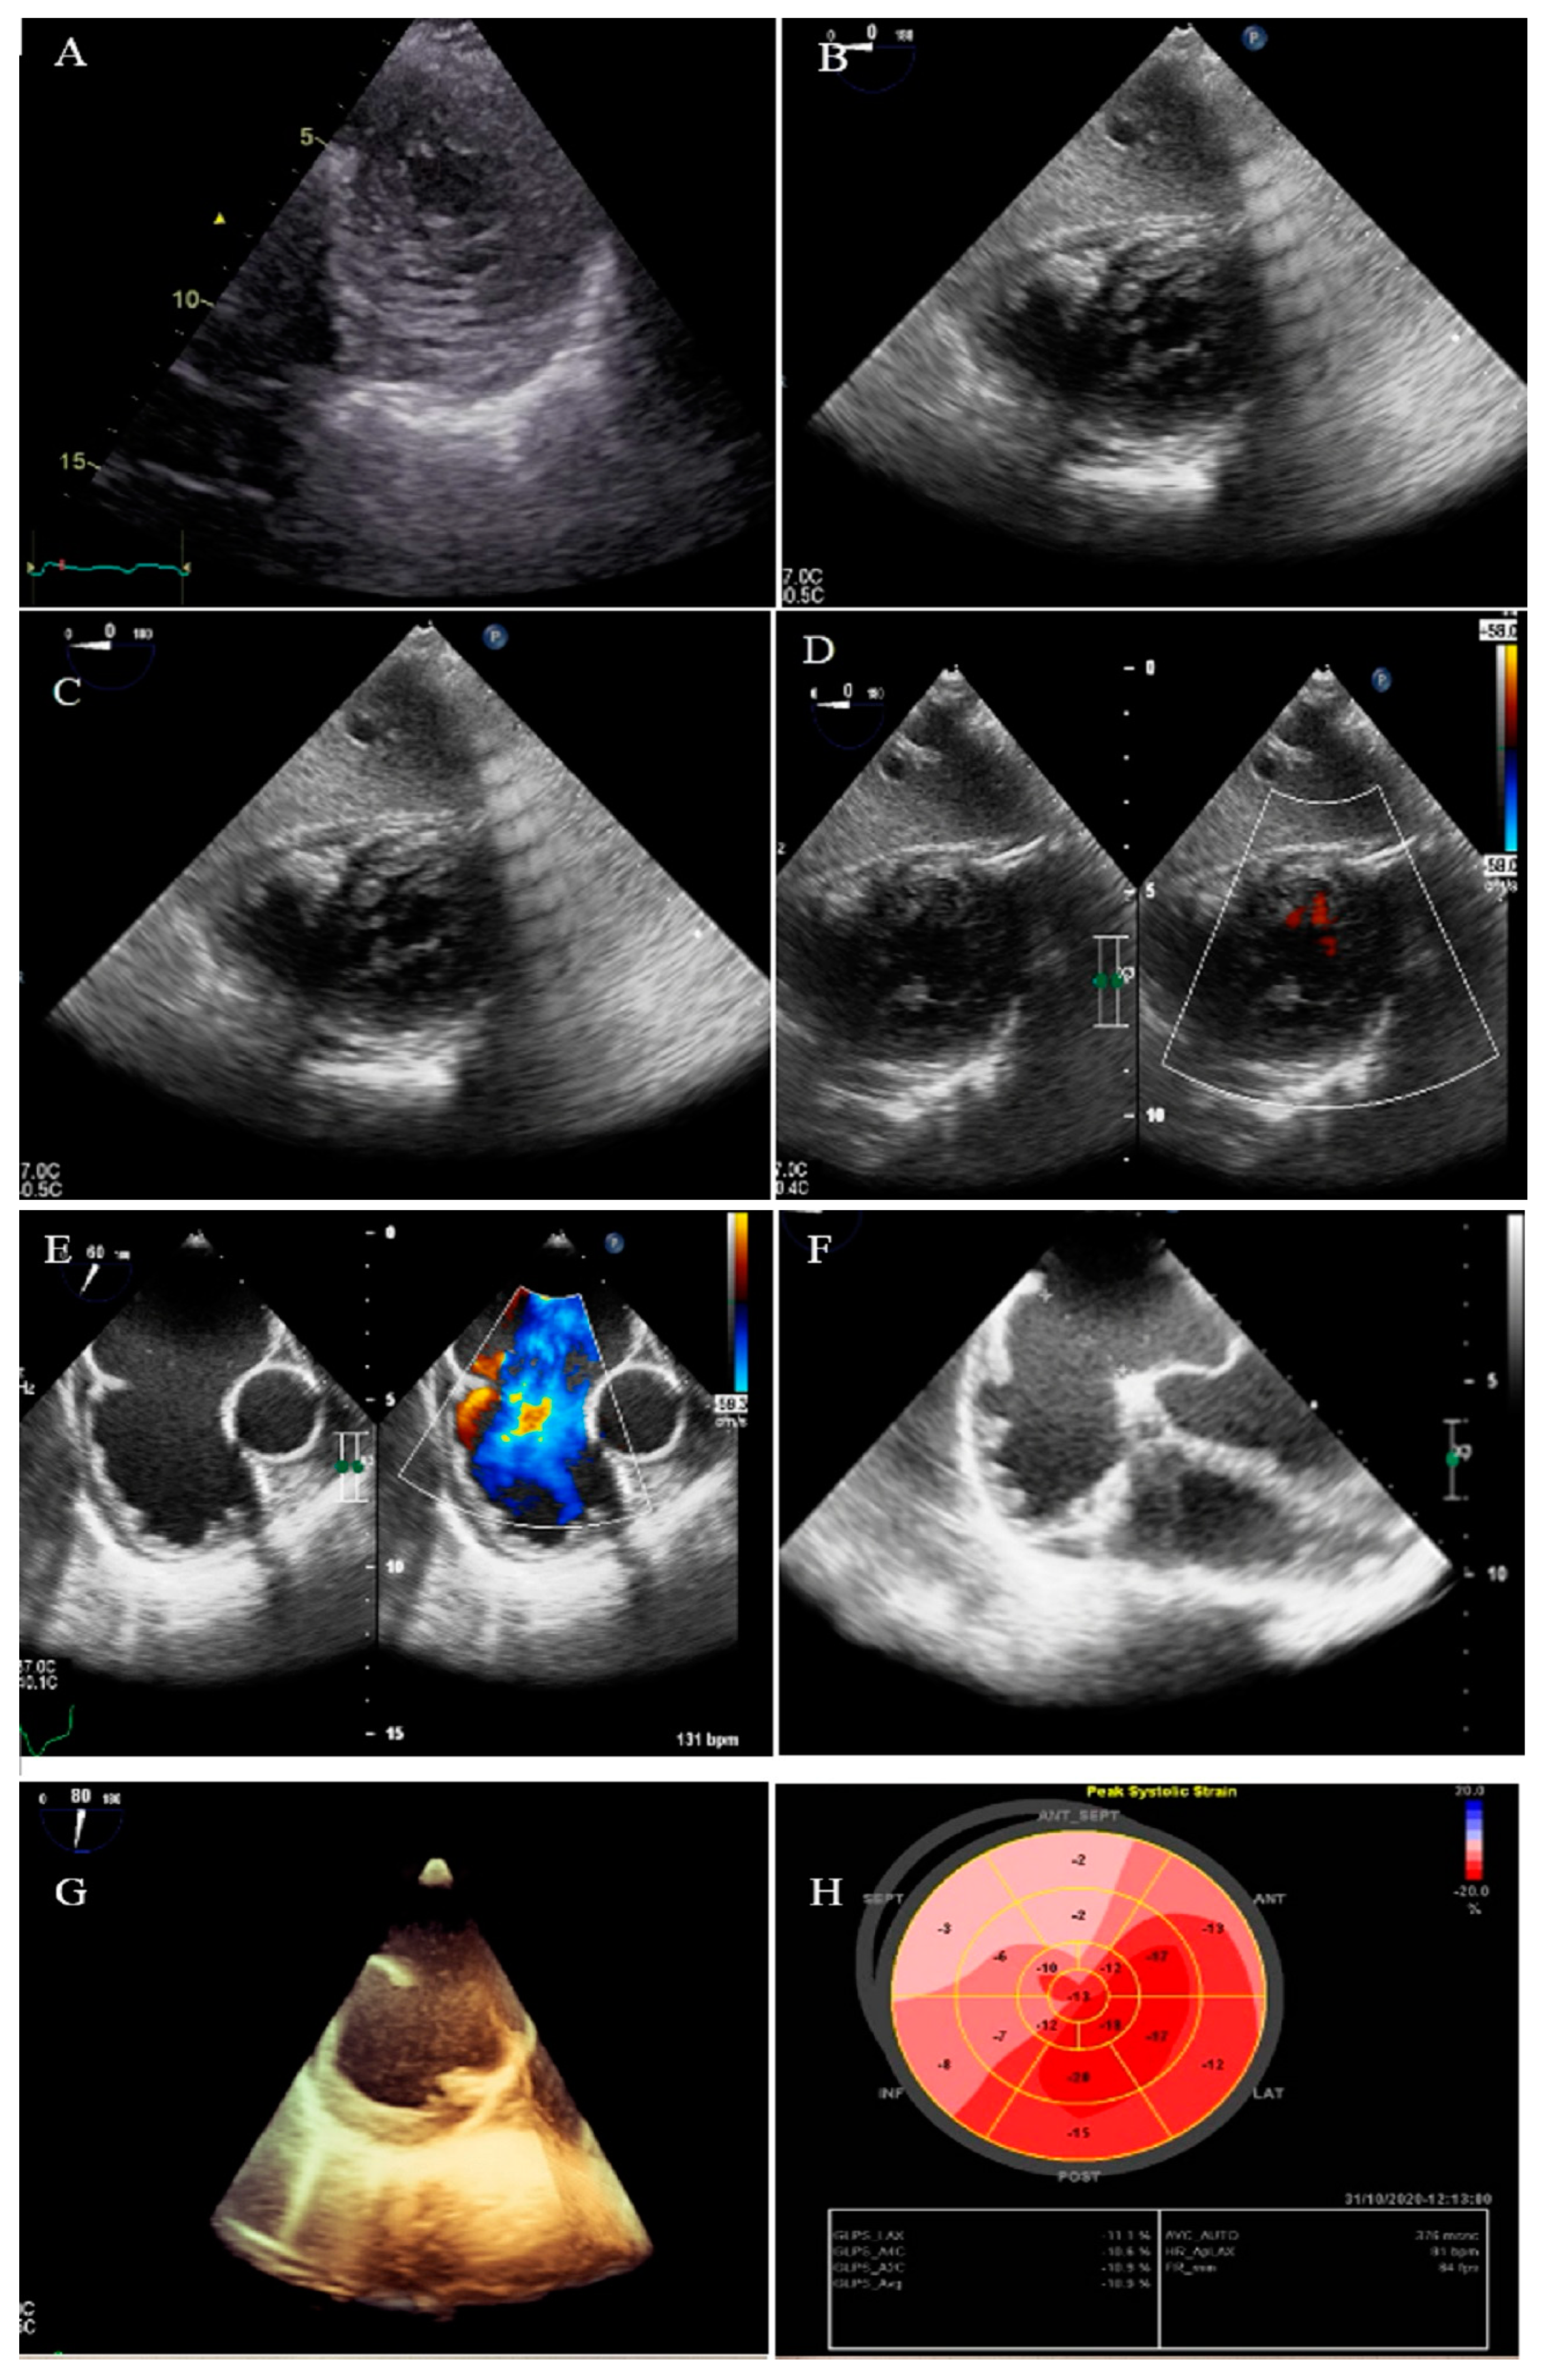

2.12. Case #12. BVNC with a Dilated Aorta

A 58-year-old gentleman was referred to our clinic with a history of palpitation and shortness of breath on heavy exercise during the past 3 months. TTE showed BVNC with normal systolic function and dilated ascending aorta (diameter = 37 mm; indexed = 22 mm). CMR was compatible with the diagnosis of BVNC (Figure S5). Low-dose carvedilol (6.25 mg three times a day) was started for the patient with the plan of OPD follow-up.

The following supporting information can be downloaded at: https://www.mdpi.com/article/10.3390/life13061231/s1, Figure S1: Two-dimensional transthoracic echocardiographic views of case #8. (A,B); Left ventricular apical four-chamber and apical SAX views, illustrating hypertrabeculated apical portions, in addition to deep intertrabecular recesses and reduced left ventricular ejection fraction (LVEF = 32%, calculated by Simpson’s method). (C); Color Doppler echocardiographic evidence of direct blood flow from the ventricular cavity into deep intertrabecular recesses. (D); PLAX showing dilated ascending aorta and PSAX illustrating bicuspid aortic valve, E; Anteroposterior directed aortic cusps. (F); Top normal size main PA in parasternal RVOT view. (G); Speckle tracking echocardiography, showing significant myocardial performance impairment in all segments with relative apical sparing; GLS= −13.1%; Figure S2: Two-dimensional transthoracic echocardiographic views of case #9. (A); Left ventricular non-compaction in SAX view, in addition to evidence of the direct blood flow from the ventricular cavity into deep intertrabecular recesses on color Doppler echocardiography, (B,C); Thick, medial-lateral directed bicuspid aortic valve. (D,E); Cardiac magnetic resonance imaging, showing prominent trabecular network in lateral segments, as well as left ventricle’s apex, consistent with left ventricular non-compaction; Figure S3: Two-dimensional transthoracic echocardiographic views of case #10. (A,B); Left ventricular non-compaction in A4C and PSAX views as well as redundant and oscillating Chiari network (white arrowhead), (C,D); Thick, unequal aortic cusps size (suggesting bicuspid aortic valve) in PLAX and PSAX views; Figure S4: Two-dimensional transthoracic echocardiographic views of patient #11. (A,B); Dilated left ventricle with apical left ventricular non-compaction in A4C and SAX views, (C); Color Doppler echocardiography, showing direct blood flow from the ventricular cavity into deep intertrabecular recesses, (D,E); PSAX view of the aortic valve, illustrating bicuspid aortic valve with a fusion between non-coronary and right coronary cusps during systole and diastole, respectively; Figure S5: Two-dimensional transthoracic echocardiographic views of patient #12. (A,B); A4C and biventricular apical SAX views, illustrating hypertrabeculated apical portions, in addition to deep intertrabecular recesses, (C); PLAX view, showing dilated ascending aorta (diameter = 37 mm), (D); Color Doppler echocardiography, showing evidence of direct blood flow from the ventricular cavity into deep intertrabecular recesses. (E,F); Cardiac magnetic resonance imaging in different views: SSFP sequence (4-chamber and vertical SA view), displaying the two-layered structure of ventricular myocardium and high signals within trabecular recesses in LV apicoanterior wall and right ventricular apex, suggestive of blood flow communicating with the ventricular cavity, (G); SA view, showing NC/C = 13.4/4.1 = 3.26 in LV apex, (H); SA view, showing NC/C = 18.4/7 = 2.62 in apicoanterior left ventricular wall, and (I); SA view, showing NC/C = 10.6/1.4 = 7.57 in right ventricular apex.